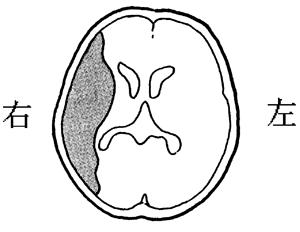

左前頭葉では非流暢性失語が見られるため、この選択肢は誤りです。左半側空間無視は、右頭頂葉後部で見られる症状です。